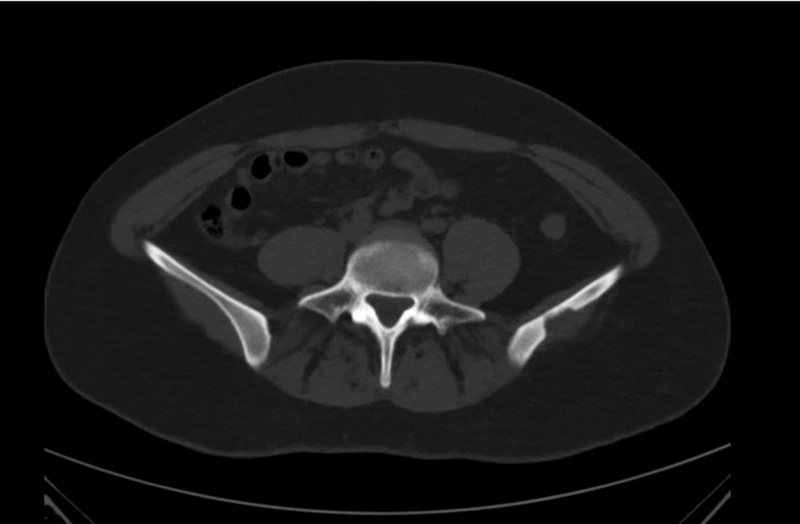

Два случая верифицированной солитарной эозинофильной гранулёмы: визуализация методами КТ, МРТ и 18F-ФДГ ПЭТ/КТ

Аннотация

В работе представлены два клинических наблюдения эозинофильной гранулёмы кости, диагностированной методами компьютерной, магнитно-резонансной и позитронно-эмиссионной томографии с 18F-фтордезоксиглюкозой, совмещённой с компьютерной томографией. В обоих случаях пациенты поступили в клинику с подозрением на первичную злокачественную опухоль кости, по результатам комплексного лучевого диагностического исследования и гистологической верификации установлен диагноз солитарной эозинофильной гранулёмы. Солитарная эозинофильная гранулёма кости ― достаточно редкое (менее 1% случаев всех опухолевых объёмных образований скелета) заболевание. Наиболее часто эозинофильная гранулёма обнаруживается в теменной и лобных костях черепа и представляет собой остеолитическое объёмное образование, постепенно увеличивающееся в размерах. Несмотря на то, что бΌльшую часть опухолей костной ткани можно выявить при помощи рентгенографии, предпочтительно применение компьютерной томографии, в первую очередь из-за её превосходной способности визуализировать деструкции кортикального слоя кости. Диагностическая точность компьютерной и магнитно-резонансной томографии может быть различна. Комплексное применение методов лучевой и радионуклидной диагностики позволяет сузить спектр дифференциального диагноза. К сожалению, относительно низкая специфичность существующих лучевых диагностических исследований в большинстве случаев не позволяет установить точный диагноз, и методом выбора остаётся биопсия с последующим патоморфологическим исследованием. Данные клинические наблюдения показывают необходимость включения эозинофильной гранулёмы в дифференциальный диагноз при обнаружении солитарного остеолитического очага.